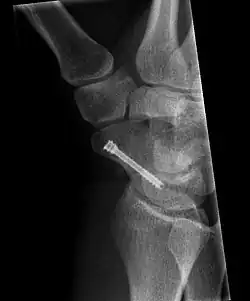

The scaphoid can be slow to heal because of the limited circulation to the bone. Fractures of the scaphoid must be recognized and treated quickly, as prompt treatment by immobilization or surgical fixation increases the likelihood of the bone healing in anatomic alignment, thus avoiding mal-union or non-union.[6] Delays may compromise healing. Failure of the fracture to heal ("non-union") will lead to post-traumatic osteoarthritis of the carpus.[1]: 189 One reason for this is because of the "tenuous" blood supply to the proximal segment.[3] Even rapidly immobilized fractures may require surgical treatment, including use of a headless compression screw such as the Herbert screw to bind the two halves together.